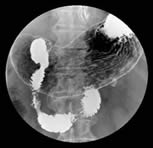

右前斜位評估胃下體部胃壁皺折及黏膜表面狀況。 |

接下來,請您躺平,以便照下仰臥位X光影像,評估胃體部胃壁皺折及黏膜表面狀況。